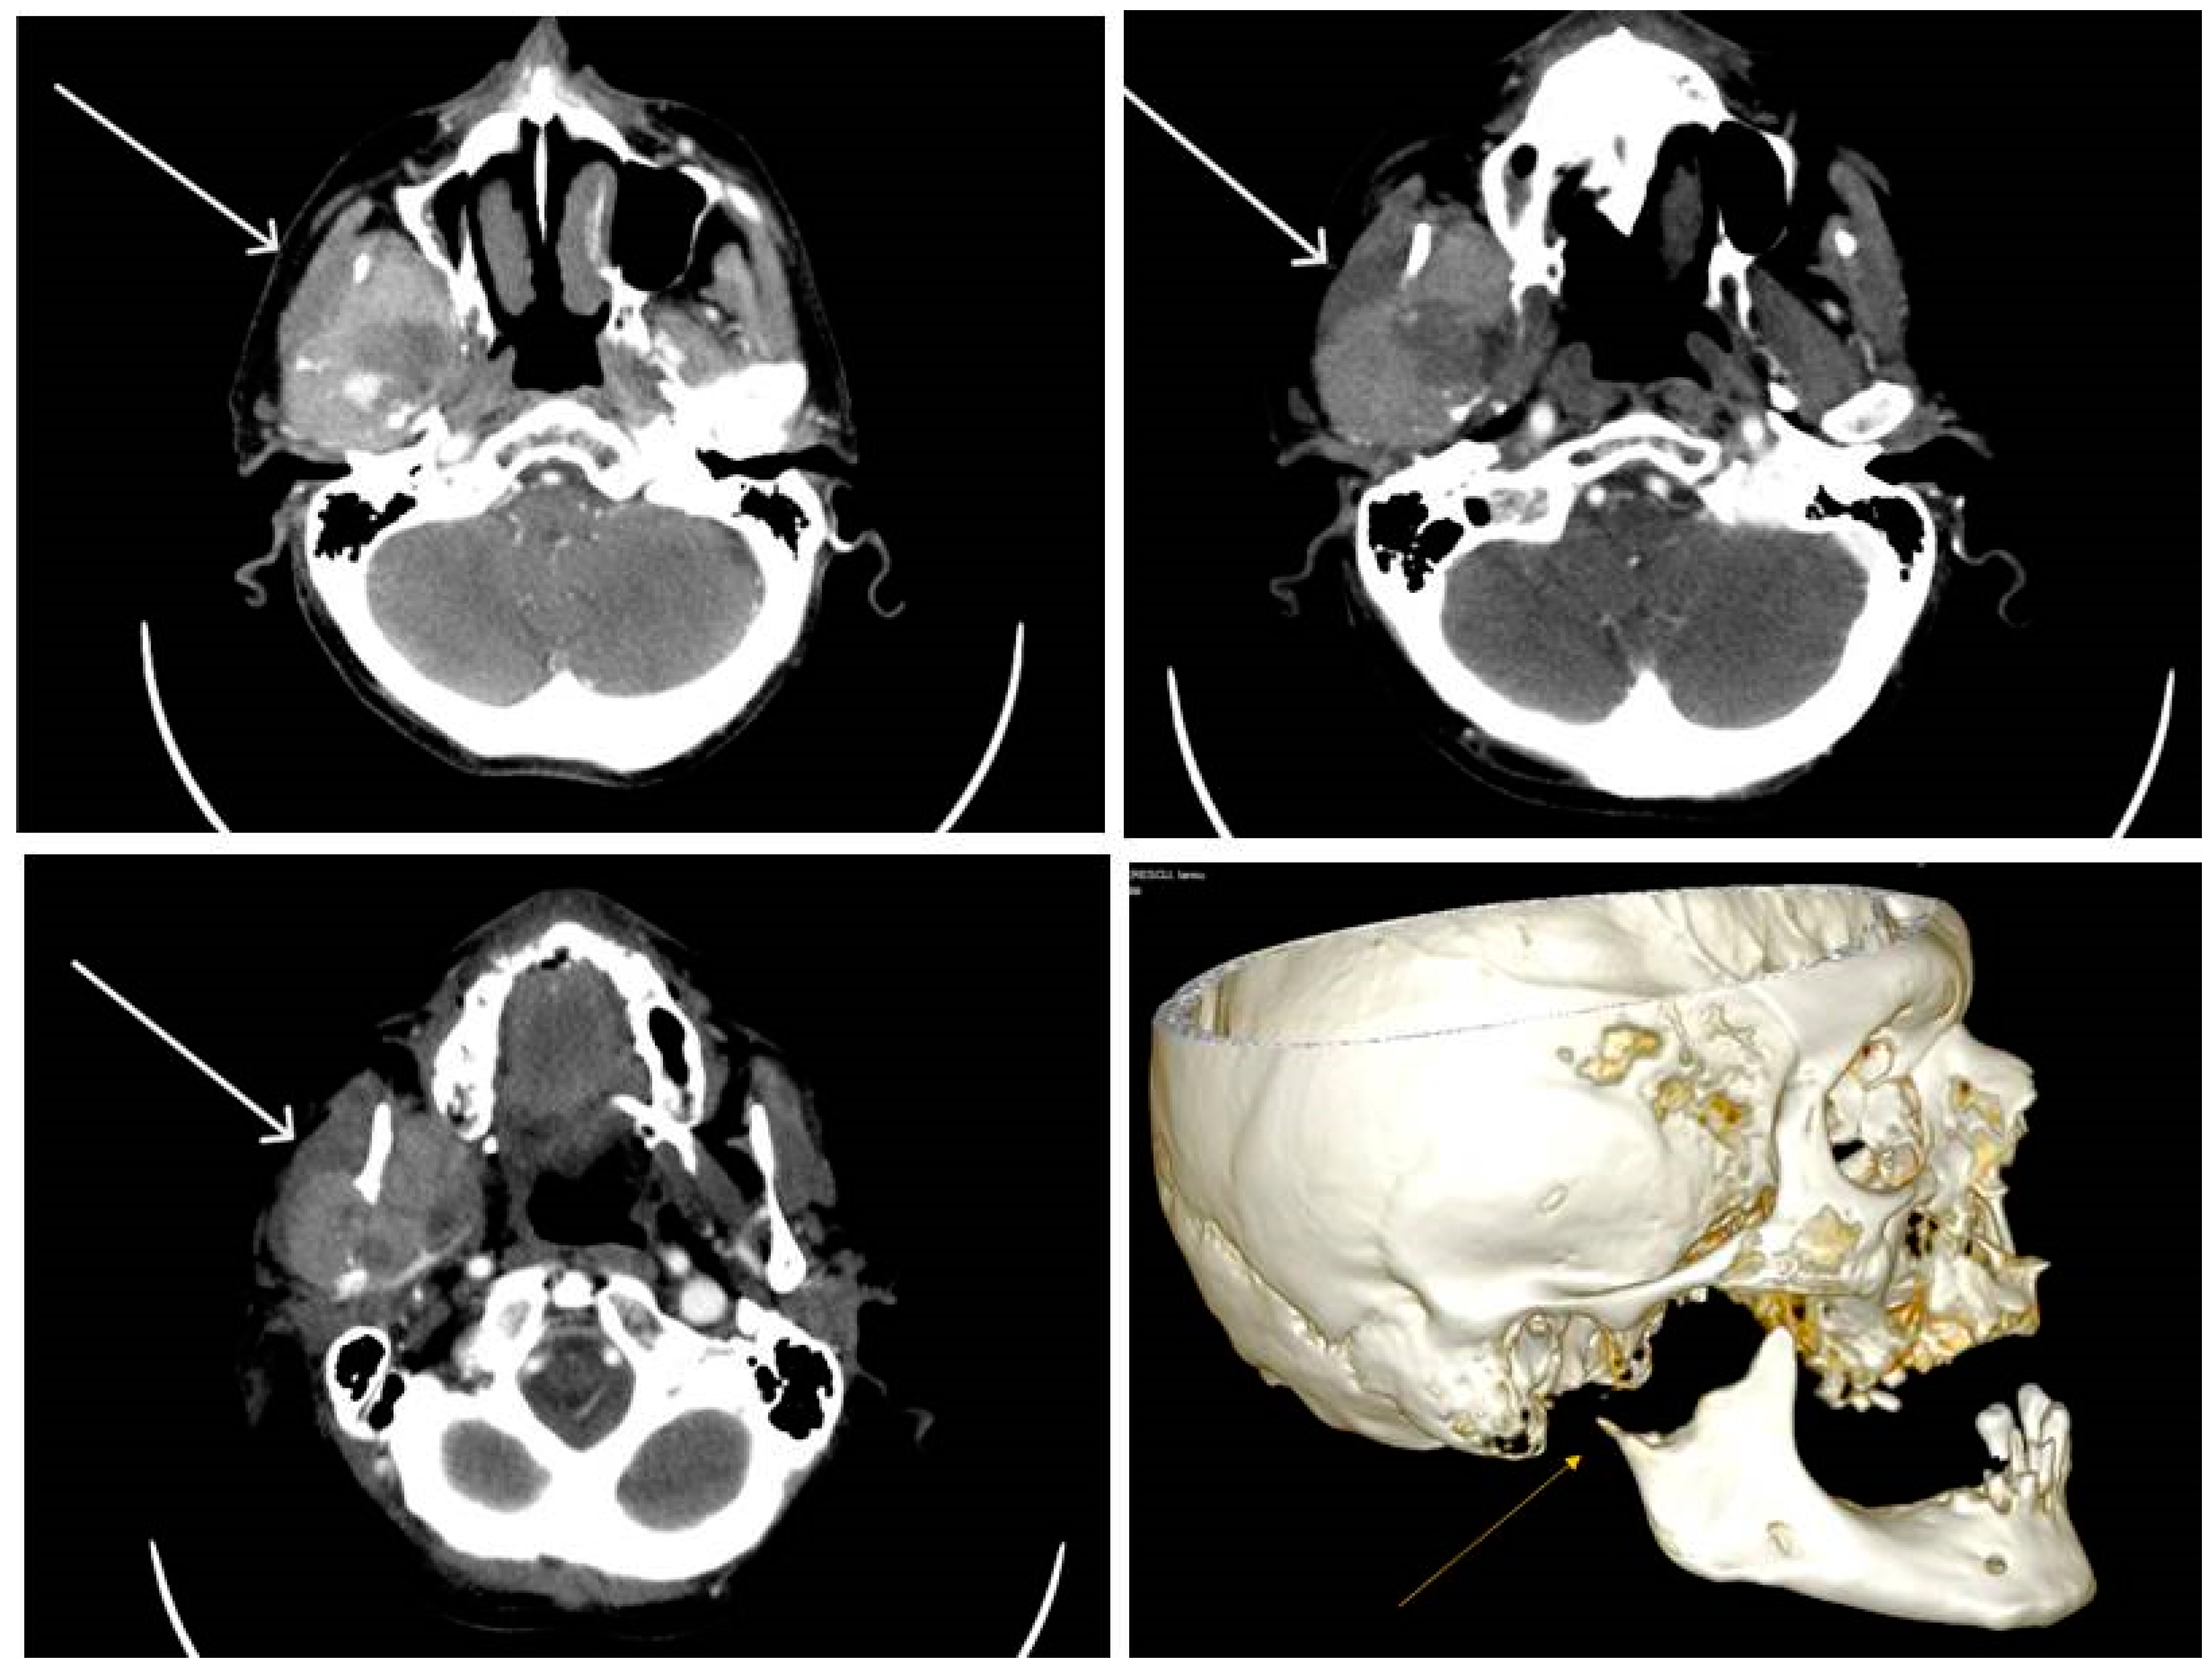

2.3.1. Clinical Findings

2.3.2. Pathological Findings